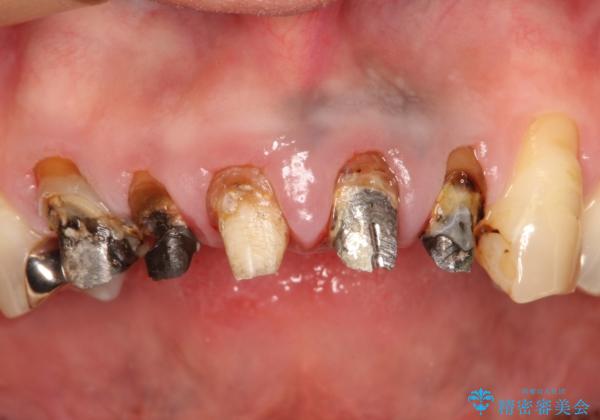

- 上の前歯の根元が黒くなっているので、再治療をしたいとのことで来院された患者様です。

適合不良のかぶせ物をすべて除去して、根の中の治療から再治療を行うこととなりました。

適合不良のかぶせ物が装着されていた歯は、内部がやはり虫歯になっていました。

かぶせ物だけではなく見えないところも、精密な治療をすることが重要となります。